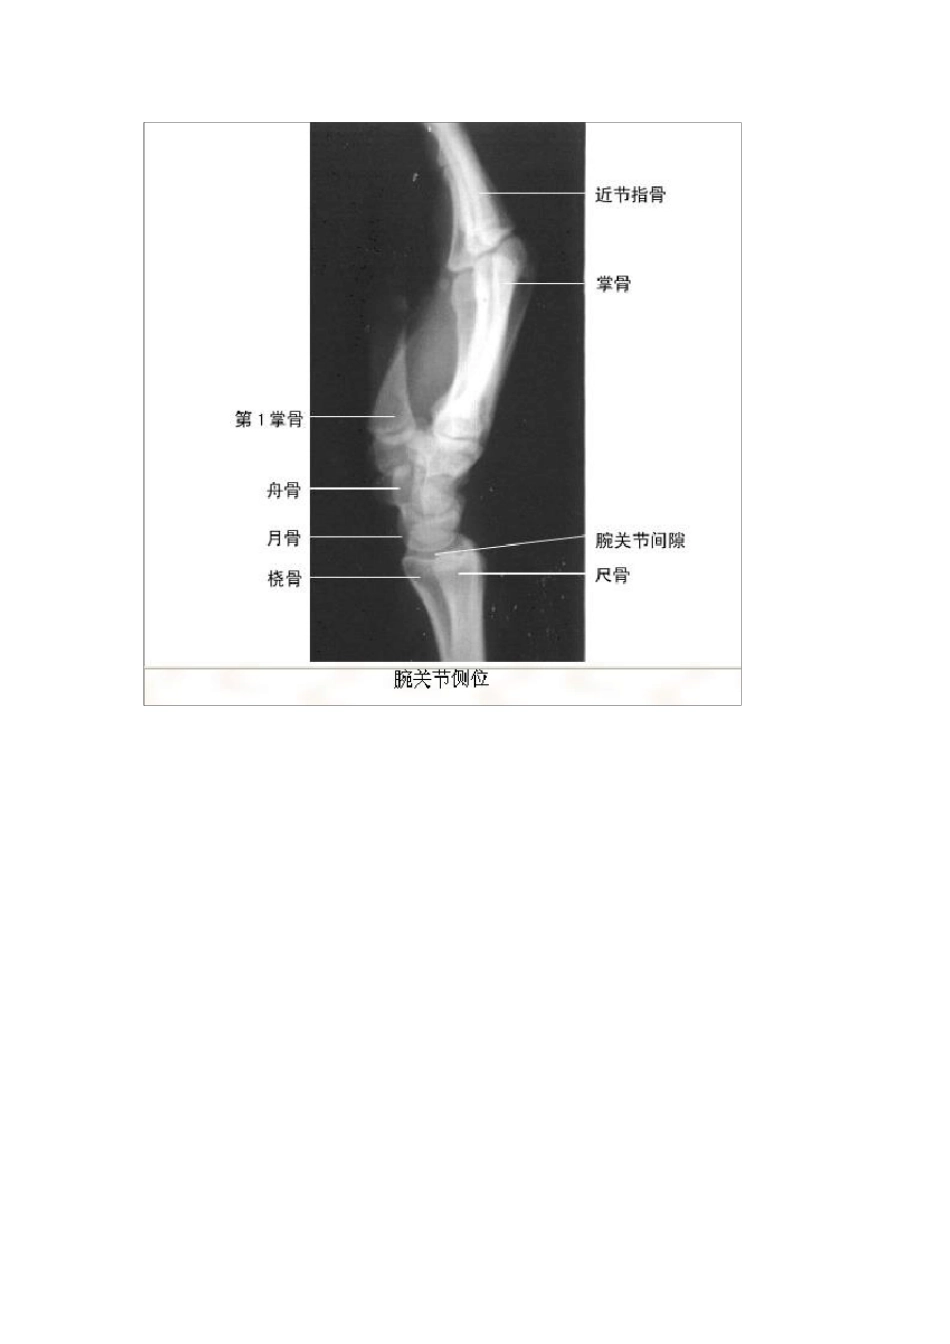

影像解剖影像图谱珍藏版